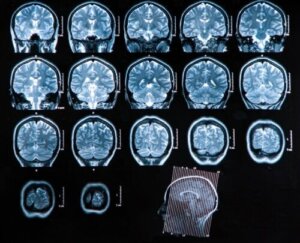

- Computertomografi: Dette har stor diagnostisk nytte, da det lar legen sjekke eventuelle koblinger med den medisinske tilstanden, og etablere behandling i henhold til den tilsvarende fasen. Denne teknikken er også en god undersøkelse for å følge opp utviklingen av patologien etter gjennomføringen av behandlingen.

- Magnetisk resonansavbildning: Dette er den beste typen avbildningsstudie for diagnostisering av en hjerneabscess. Det er mye mer følsomt enn datatomografi og gir mange fordeler ved påvisning av tidlig cerebritt, og ødem og bedre differensiering mellom områder med betennelse og andre berørte strukturer.